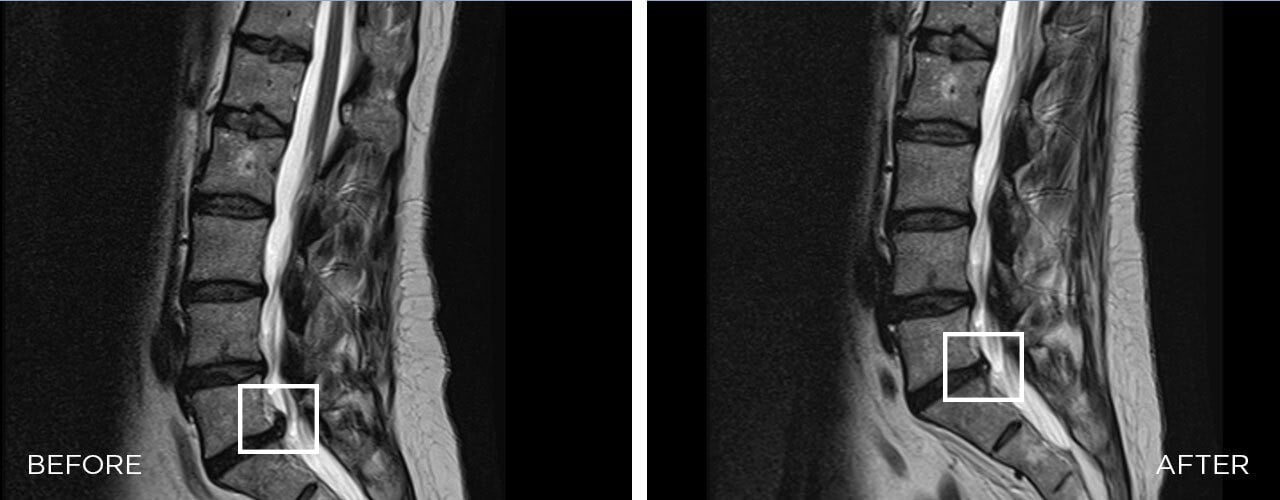

The BTL SPINAL DECOMPRESSION is a mechanical therapy that uses automated decompressive forces to mobilize joints, relieve the pressure over neuro-spinal structures, and relax and elongate soft tissues.

The therapy is based on the targeting decompressive forces applied over vertebrae. Decompressive forces occur as automated and controlled cycles which leads to enlargement of intradiscal spaces, enhanced blood perfusion, disc rehydration, and realignment of vertebrae.Â

Yes it is. Decompression therapy brings pain relief through enlargement of intradiscal spaces, enhancement of blood perfusion, rehydration of the discs, and realignment of impaired vertebrae.